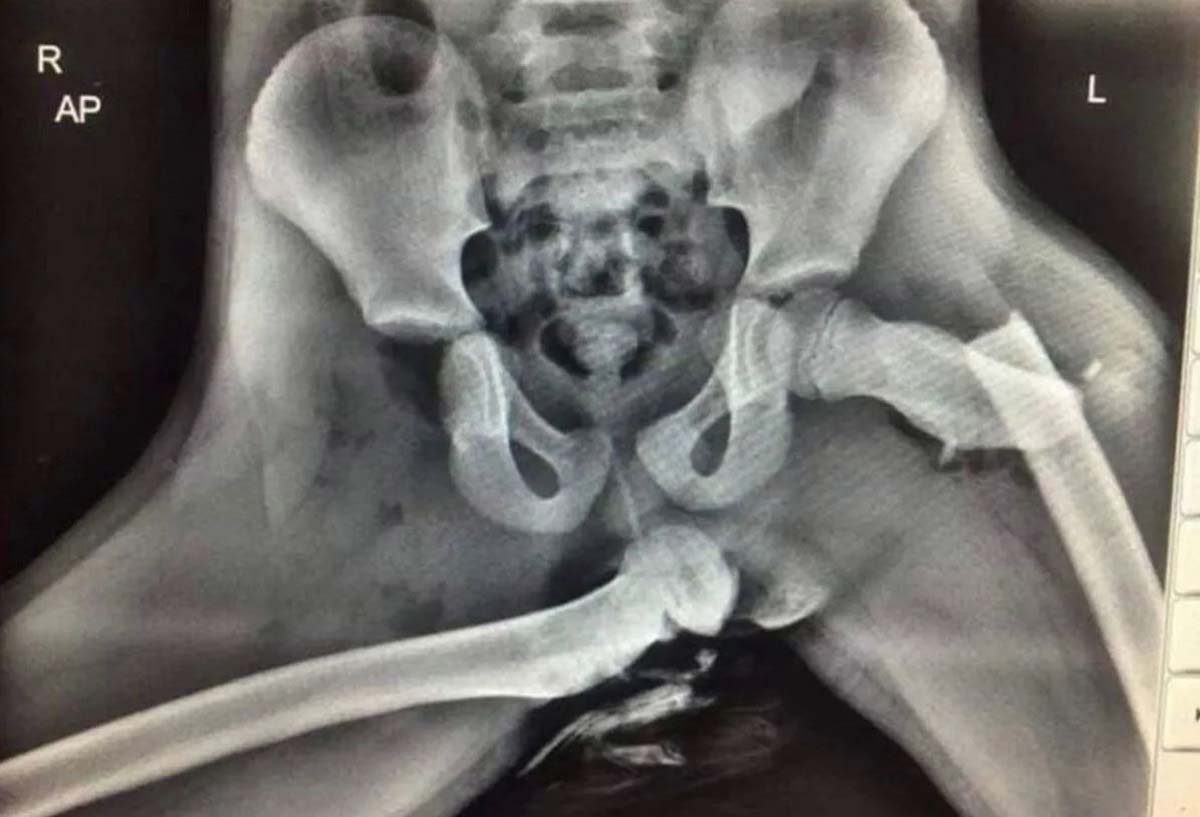

자동차 앞좌석에 앉아 대시보드에 발을 올리는 행동은 사고 발생 시 큰 부상으로 이어질 수 있어 위험하다. 실제로 호주 도로 및 해양 서비스 충돌실험실(Road and Maritime Services Crashlab) 연구팀은 대시보드에 발을 올렸을 때 사고가 발생하면 어떻게 되는지 실험했다. 실험 결과, 자동차가 시속 70km(43.5mph)로 벽에 충돌하면 에어백이 터지면서 마네킹의 다리가 얼굴 쪽으로 접혔다. 게다가 마네킹이 안전벨트 아래로 미끄러져 벨트에 의한 손상도 동반됐다. 연구팀은 실제 사람이 탑승했으면 장 파열, 대동맥 파열, 척추 골절 등 내부 장기 부상으로 이어졌을 것이라고 추정했다. 2020년에는 영국의 한 경찰이 대시보드에 발을 올려놓았던 피해자의 엑스레이 사진을 공개해 이 습관을 경고하기도 했다. 해당 엑스레이 사진에서 피해자는 골반이 완전히 탈골되고, 다리에도 골절상을 입었다.